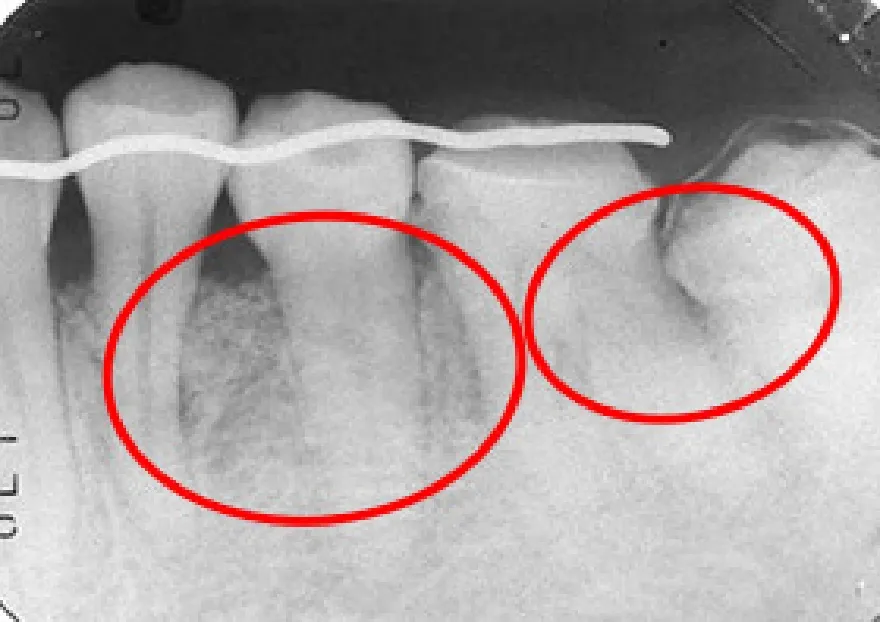

• 治療前

• 治療後

GBR(骨再生誘導法)とは、欠損した骨組織を特殊な膜等を用いて再生させる治療法です。

骨が失われた部位を特殊な膜で覆って上皮の進入を防ぎ、骨の自己再生能力を最大限に高めて再生を促します。

GBR法を応用すれば、顎の骨がやせてインプラントが出来なかった部位にもインプラントを埋入することが可能になります。